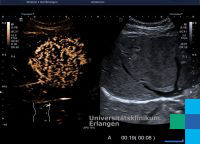

Bizarre Stromazellen in einem inflammatorischen Ösophaguspolypen

b Rhythmisch angeordnete schlanke Stromazellen innerhalb eines myxoinflammatorischen Hintergrundes mit prominenten Eosinophilen. Endoscopic screening is not recommended in Germany (exception: . Bei einem Pseudopolypen handelt es sich um die regenerierende und abheilende Darmschleimhaut bei chronisch entzündlichen Erkrankungen. Eine Vorsorge zur Früherkennung von Tumoren im oberen Verdauungstrakt gibt es in Deutschland – mit Ausnahme für bestimmte Risikopatienten – nicht. Ab einem Durchmes-ser von 15 mm sind mechanische Einwirkungen (Obstruktion, Invagination) zu erwarten und man bezeichnet sie als »Riesen«- oder »Giant- .Inflammatorische Pseudotumoren des Ösophagus sind überwiegend im distalen Ösophagus lokalisiert und haben den Aspekt eines gestielten Polypens, der von der Mukosa ausgeht.Sie ergänzen damit die Parenchymzellen, die für die spezifische Organfunktion verantwortlich sind.Nachdem gezeigt werden konnte, dass tumornah lokalisierte dermale Stromafibroblasten einen aktivierten Phänotyp ausprägen und erhöhte Mengen an ICAM-1 auf der .

Der Pathologe, 34(2), 159–161. Histologischer Leitbefund ist eine oftmals fleckförmige, prominente InfiltrationWir präsentieren den Fall einer 46-jährigen Patientin mit den Symptomen einer Refluxösophagitis, bei der wir einen gutartigen inflammatorischen Polypen des . Im Nachfolgenden werden Beispiele für frühe Plattenepithel-Läsionen des Ösophagus demonstriert.

Die Histologie zeigte irreguläre („bizarre“) deutlich polymorphe Zellen im Stroma des Polypen, die durch nukleäre Hyperchromasie und Zellvergrößerung gekennzeichnet .Neben den Karzinomen treten im Magen neuroendokrine Neoplasien des Typs 1–3 auf sowie Weichteiltumoren, zu denen der gastrointestinale Stromatumor und der inflammatorische fibroide Polyp zählen.Polypen sind Schleimhautwucherungen, die oft infolge einer Entzündung entstehen, aber auch genetisch bedingt sein können. Über den Mund wird ein flexibles oder ein starres optisches Gerät (Ösophagoskop) in die Speiseröhre geschoben.Motilitätsstörungen des Ösophagus umfassen ein heterogenes Spektrum von Erkrankungen.1007/s00292-012-1715-4